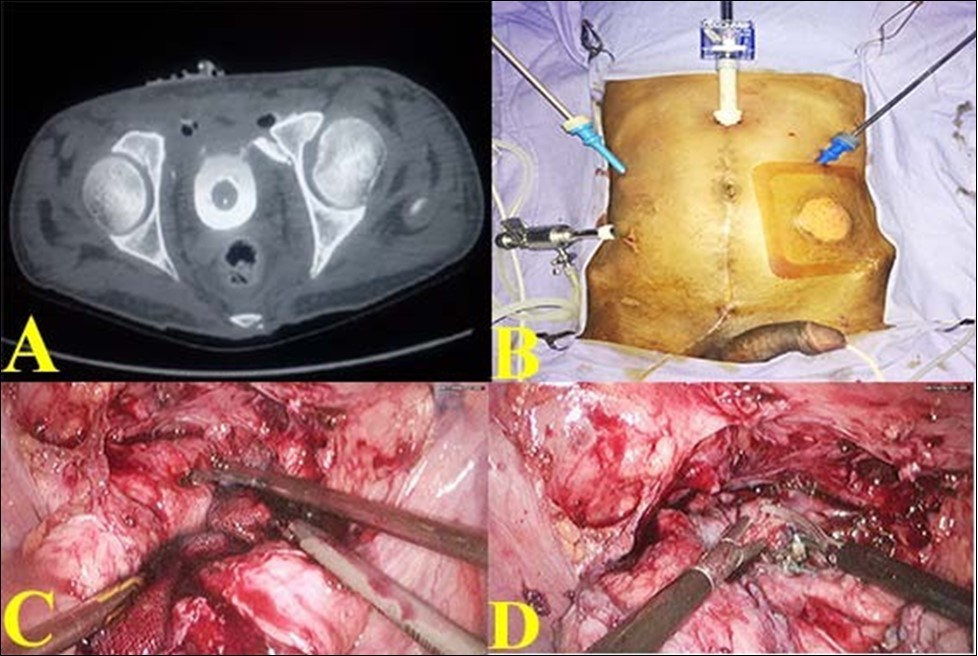

17-year-old male was referred with a urethral and suprapubic catheter and complaints of fever and pyuria for 6 weeks. The prior record showed that he was admitted 2 months earlier following a road traffic accident with pain in the lower abdomen, hematuria and anal tear. He was initially stabilized and was evaluated with a CT scan which showed a pelvic fracture; extra-peritoneal bladder injury at two sites in the antero-lateral wall. The attending trauma surgeon did diverting colostomy for anal tear and supra-pubic cystostomy. Patient was referred after 6 weeks of fever and pyuria. Clinical examination revealed fair general condition and abdomen examination revealed a well-healed midline laparotomy scar along with colostomy, supra-pubic and urethral catheters. Bio-chemical investigation revealed normal renal function. Urine culture was positive and he was treated with culture specific antibiotic as he was symptomatic. After 7 days of treatment, computerized tomographic cystogram was done, which showed bilateral extra peritoneal bladder tears of about 15mm in length with extravasation of contrast from the anterolateral wall of bladder close to bladder neck bilaterally. Figure 1(A). Considering the persistence of gross extravasation of bladder contrast even after 7 weeks; laparoscopic repair of the bladder rent was planned.

Sigmoid colostomy was covered with sterile adhesive. With the patient in supine position, using 4 ports, laparoscopy was done. Figure 1 (B). There were extensive omental and bowel adhesions, which were released. Bladder was dropped and the SPC was removed. Extensive fibrosis was noted between the anterior wall of the bladder and pubic bone. Further mobilization of anterior wall of bladder revealed a bone spicule impinging on the left anterolateral wall and causing a rent of about 15 mm. The other rent was noticed on the right anterolateral wall close to the bladder neck about 15 mm long. Figure 1 (C). The bone spicule was removed.

Diluted methylene blue solution was instilled through urethral catheter to confirm that there were no other rents. The two rents were connected and made into a single large rent. Figure 1 (D). The edges were trimmed and closed using 3-0 absorbable barbed suture and omentum was tacked over the suture line.

Figure 1.A. Pre-operative CT showing contrast extravasation in anterior wall with bony spicule; B. Port Placement for bladder repair; C. Bladder rent identified by methylene blue; D. Two defects joined into a single cystotomy